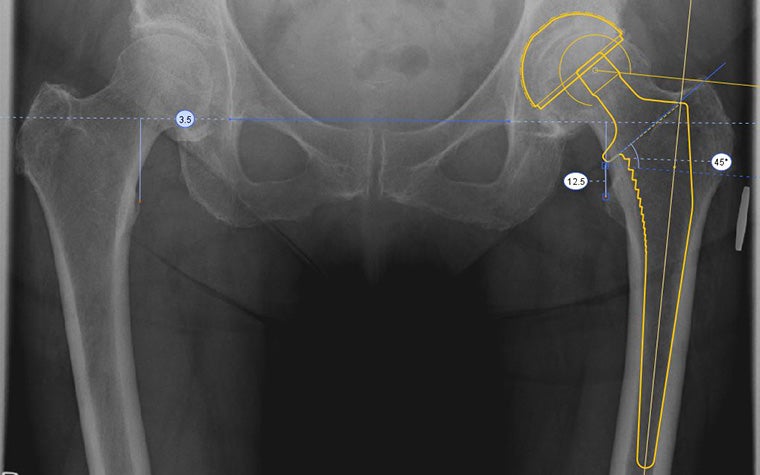

Join this training course for a quick start in digital templating using one of the most trusted planning tools in the market, Materialise OrthoView, which has a 96% planning accuracy in THA. You'll learn how to perform the most optimal workflows for planning total hip replacement and total knee replacement procedures.

- How to scale X-ray images, analyze biomechanics, and template for knee and hip replacement

It will give you the foundation to learn templating using X-ray scaling, analysis tools, and smart templates.